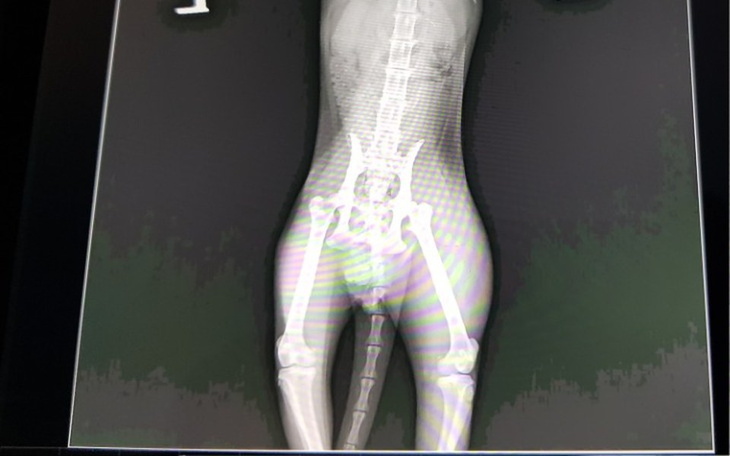

Nitka to jednak chłopczyk Nitek. Ale nie o płeć tutaj chodzi. Najświeższe informacje nie są dobre. Lekarze podejrzewają krwawienie wewnętrzne. W dniu jutrzejszym zaczyna się pełna diagnostyka. Zaprzyjaźniony gabinet będzie miał twardy orzech do zgryzienia. Oby nie sprawdził się czarny scenariusz. Trzymajcie kciuki. Operacja w takim stanie niesie ogromne ryzyko, ale będzie to zabieg ratujący życie ☹️ oby nie był potrzebny 😰

W dzień, gdy wszyscy szykowali się na imprezy andrzejkowe, ta chudzinka postanowiła szukać pomocy. Ostatkami sił weszła do budki dla kotów wolnożyjących. Chuda jak szkapa z urazem miednicy, nie potrafiąca stanąć na tylne łapki, z mega dużą biegunką... Cały on...

Kot jest w stanie złym, rokowania ostrożne. Nie można póki co poddać go dalszej diagnostyce, gdyż obecnie walczy o życie. Jego chude i wątłe ciałko musi odbić się. Jest karmiona wysokomięsnymi puszkami, żeby przyspieszyć ten proces. Dostaje również leki.